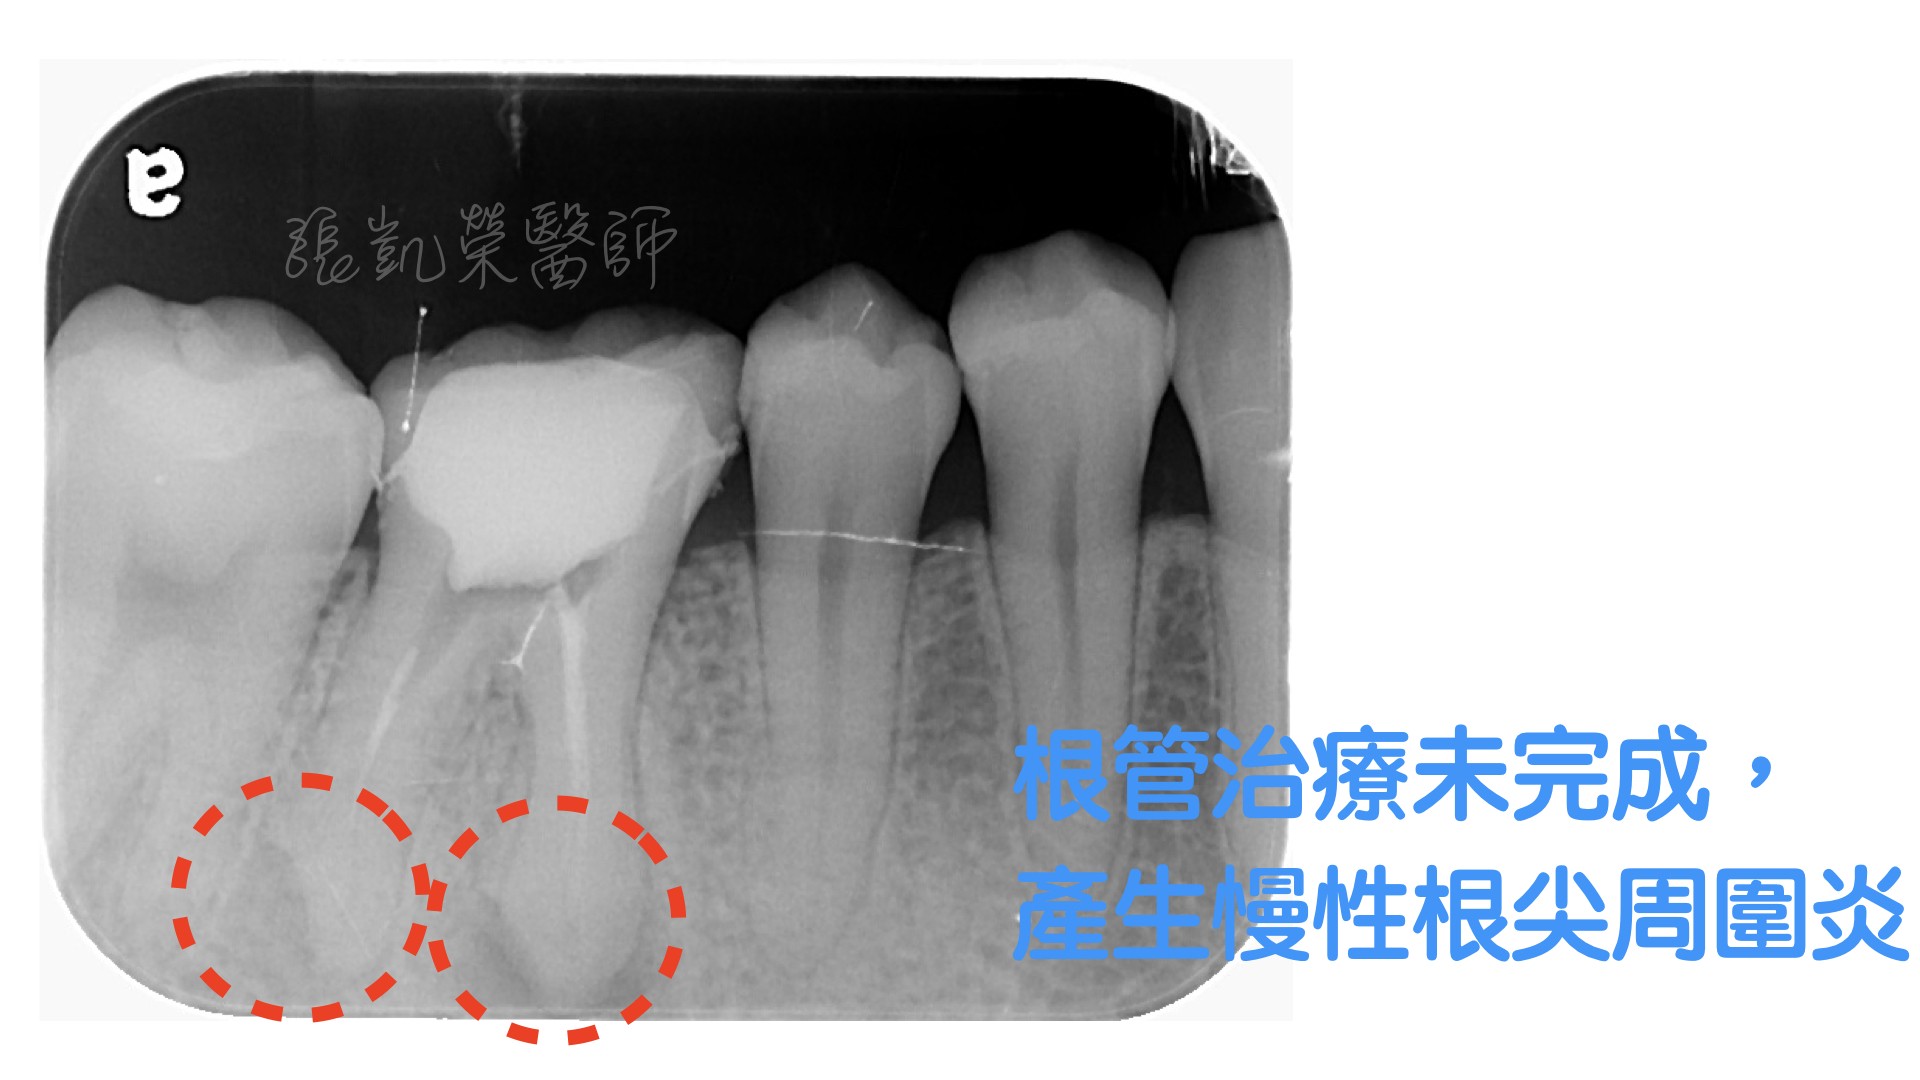

當牙髓受感染,需要將牙髓腔裡的牙髓清除,如果有未清除乾淨的殘髓,長期下來,可能會造成細菌累積,在根尖造成骨頭的破壞。

先拆除原有牙冠或是柱釘,再利用顯微鏡,將牙髓腔重新清創,移除根尖的感染源,等確定根尖已經清除乾淨,再將重新製作牙冠覆蓋上去。